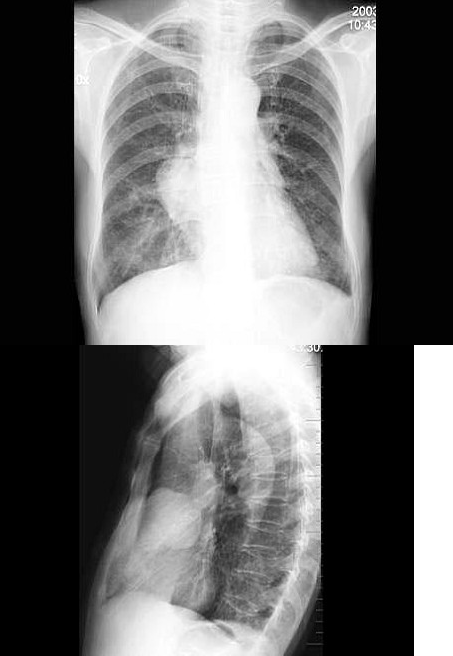

26、单项选择题

女,57岁,胸痛,咳嗽1月余,不发热,咳白色痰,无痰中带血,X线检查如图,最可能的诊断是()

A.右侧肺不张

B.右肺炎症

C.纵隔肿瘤

D.右肺肿瘤

E.右肺结核